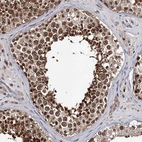

Immunohistochemical staining of human testis shows strong cytoplasmic positivity in cells in seminiferous ducts.